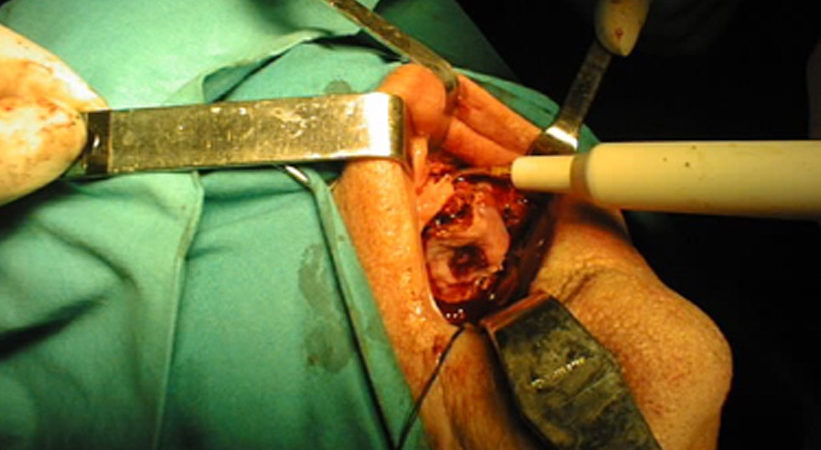

Donna di 76 anni portatrice di un carcinoma squamoso del trigono retromolare infiltrante l’osso mandibolare T4N0.

La paziente è stata sottoposta ad intervento “commando”.